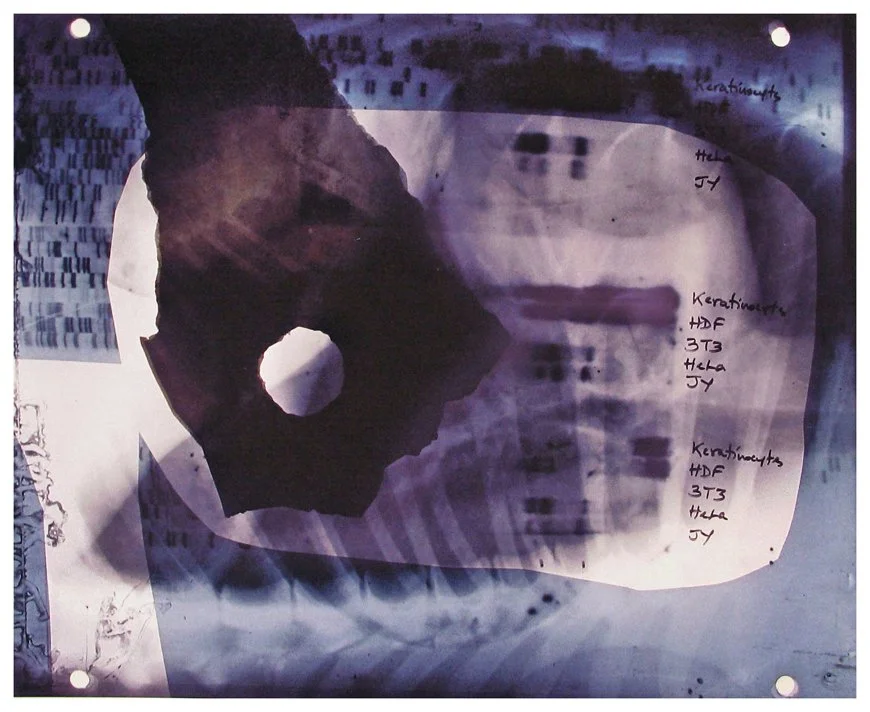

Insight is a series of collaged X-ray fragments, which were digitally composed into giclée prints. They speak not only of the body’s interior, but of the human experience it contains.

Drawn from DNA sequencing gels, mammograms, ultrasound scans, and cell cultures grown in Petri dishes, these compositions reframe diagnostic materials as metaphoric landscapes. What once served to identify illness becomes a language of line, texture, and light. They serve as a quiet meditation on fragility, resilience, and the unseen forces that shape us.

Each image in Insight is both an anatomical artifact and an artistic inquiry. Each one is part of my ongoing exploration of the relationship between Art, Science, and Medicine. Through digital layering and compositional play, I aim to dissolve the boundary between clinical detachment and emotional intimacy by inviting viewers to look inward and find meaning in the microscopic.